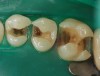

Figure 1. A large defective amalgam on the first molar with severe wear surrounding it.

Figure 1

Case 1 (Figure 1 through Figure 6) reveals a mandibular first molar with severe wear and a defective amalgam. The amalgam and decay were removed, the tooth was prepared, and bonding to enamel and dentin was completed. An initial layer of composite was placed and cured, followed by many subsequent layers to minimize the negative effects of shrinkage. The composite was shaped and initial polishing was completed. Occlusion was adjusted, final shaping was accomplished and polishing was completed.